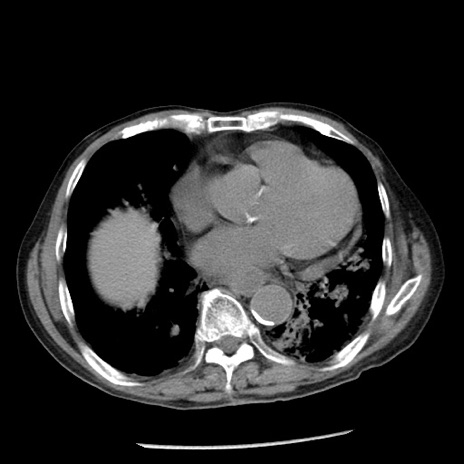

症例26(横断像)

【症例】80歳代男性

【主訴】嘔吐

【現病歴】昨晩2回嘔吐あり、今朝になっても嘔吐あり。来院。

【既往歴】胃潰瘍

【身体所見】意識清明、BT 37.6℃、BP 166/95mmHg、HR 100bpm、SpO2 97%、腹部:平坦・軟、腸蠕動音聴取良好、圧痛なし。

【データ】WBC 21900、CRP 1.46